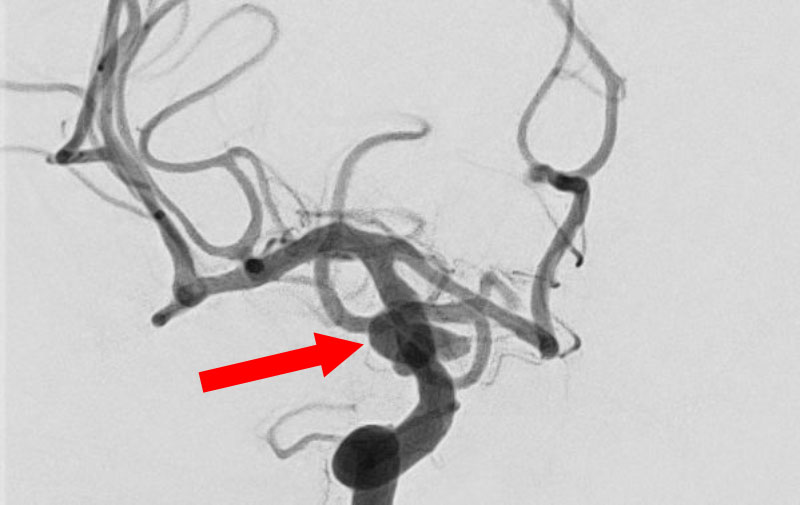

くも膜下出血

左中大脳動脈瘤破裂

40代

救急外来

No.1596 手術前

No.1596 手術後